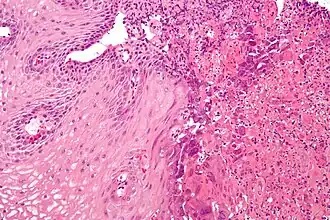

Морфологические формы эзофагита

| Катаральная форма | Характеризуется гиперемией и отёчностью слизистой оболочки пищевода. Наиболее распространённая форма эзофагита. |

| Отёчная форма | Характеризуется гиперемией и отёчностью слизистой оболочки пищевода. Наиболее распространённая форма эзофагита. |

| Эрозивная форма | Чаще всего развивается при острых инфекционных болезнях и действии на стенку пищевода раздражающих веществ. |

| Геморрагическая форма | Развивается при некоторых инфекционных и вирусных болезнях (например, при сыпном эпидемическом тифе, гриппе). |

| Псевдомембранозная форма | Наблюдается при дифтерии, скарлатине. При этой форме фибринозный экссудат не спаян с подлежащими тканями. |

| Эксфолиативная форма | Наблюдается при дифтерии, скарлатине. При этой форме фибринозный экссудат прочно связан с подлежащими тканями. |

| Некротическая форма | Встречается при тяжёлом течении инфекционных болезней, таких, как корь, скарлатина, брюшной тиф и др., а также при кандидозе, агранулоцитозе, сопровождается образованием глубоких язв. |

| Флегмонозная форма | Образуется в результате внедрения в стенку пищевода инфицированного инородного тела, процесс может распространиться вдоль пищевода и в сторону средостения. |